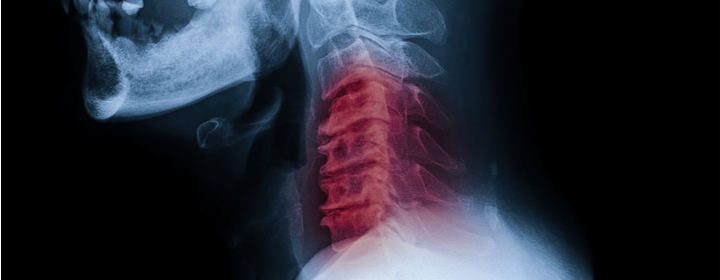

The cervical spine consists of the cervical vertebrae with cervical discs in between. It supports the head and provides the flexibility you need to turn your neck from side to side and rock it from front to back. The cervical discs, composed of collagen and ligaments, carry the bulk of the workload by acting as shock absorbers between the cervical vertebrae, holding the vertebrae together and allowing for the movement of the neck. This area of the spine also provides the path for blood flow to the brain. When you hear about C1, C2, C3, C4, C5, C6, and C7, you are hearing about the area known as the cervical spine.

Trauma to the cervical spine and nerves can result in pain, numbness, tingling or the functional loss of the diaphragm, shoulders, biceps, arms, wrists, hands and fingers.